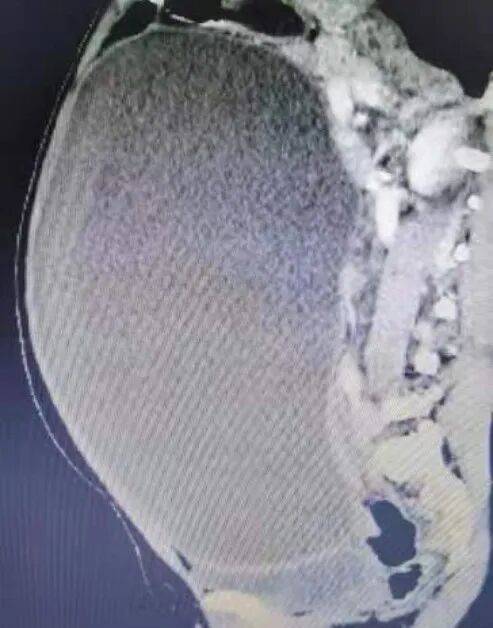

入院前,黃女士腹部膨隆,就像懷孕6個月的樣子,在門診做了彩超提示:腹腔巨大腫物,性質(zhì)待查,醫(yī)生建議住院查明原因。入院后,患者進(jìn)一步完善CT檢查,結(jié)果提示:腹腔巨大囊性腫物,性質(zhì)待定,漿液性囊性瘤。

患者的腹部及CT影像

從CT上看,腫物實在太大,充滿了整個腹腔,把周圍的臟器都擠壓到一邊。這個腫物究竟是什么?從哪里來?肝膽外科組織多學(xué)科討論,認(rèn)為囊腫來源于大網(wǎng)膜、腸系膜、卵巢這三個地方的可能性較大,決定由余靜喜醫(yī)生及張相森醫(yī)生為患者實施“剖腹探查+腹腔巨大腫物切除術(shù)”。